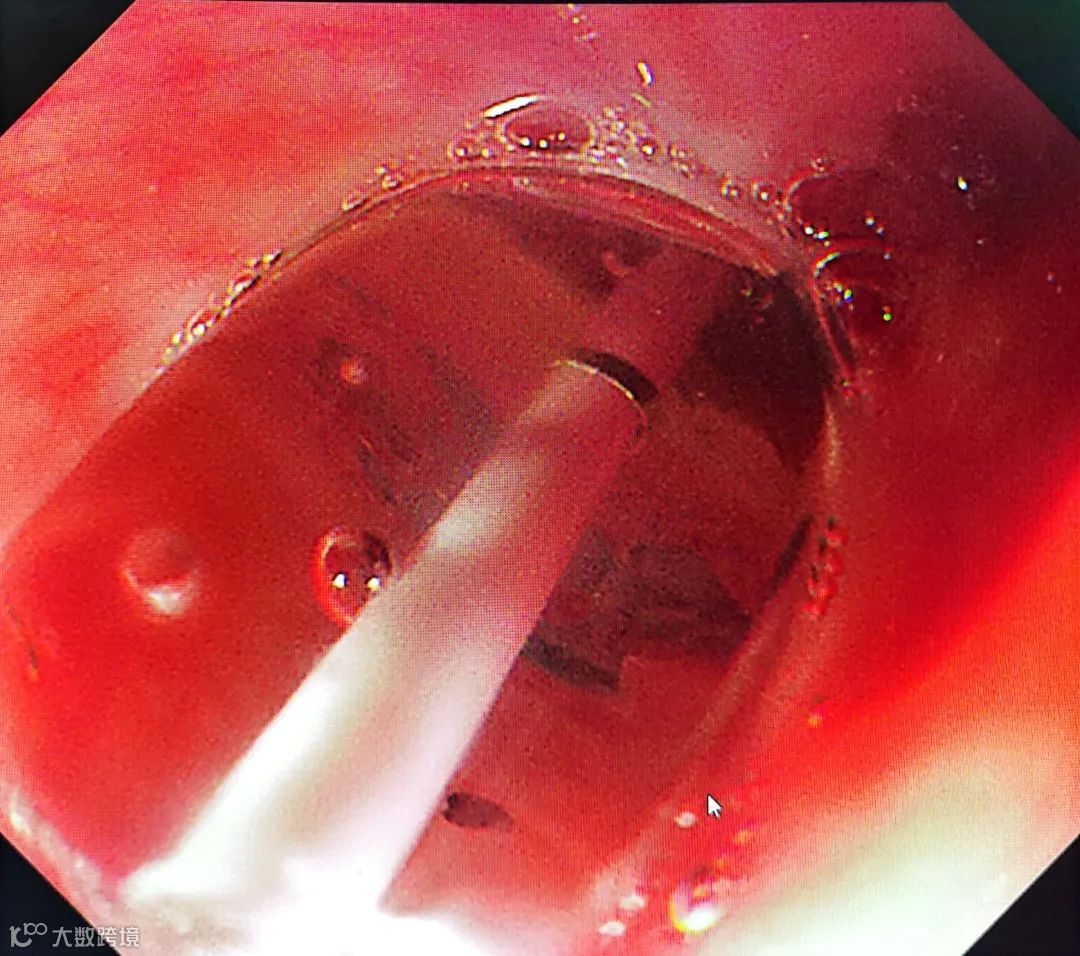

球囊扩张术简单来说就是在食管内放进去一个小球,充气将食管扩开,然后再将球内的气体抽出,将球取出体外,达到扩张食管的目的。

内镜下食管狭窄球囊扩张术

手术只用了不到20分钟

过程顺利

通过手术

王奶奶的食管吻合口

由0.4厘米扩张到了1.4厘米